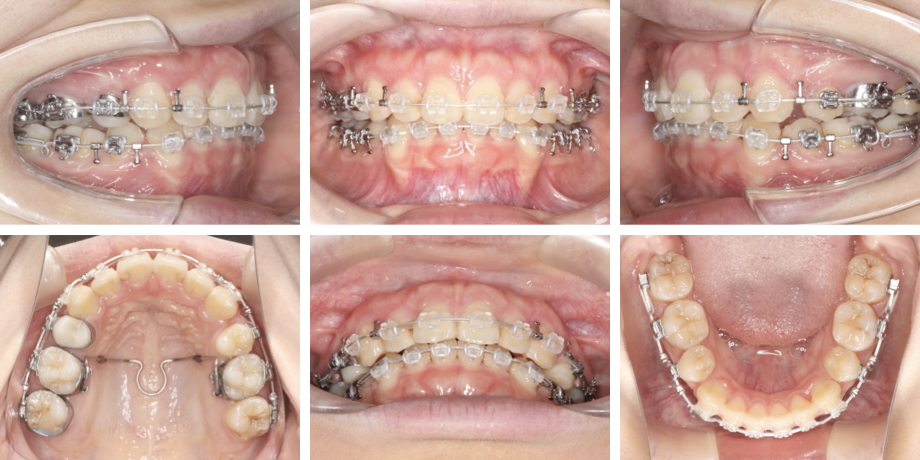

治療開始10か月

治療終了(治療開始1年6か月)

• 4.治療のカテゴリー:本格治療

• 5.抜歯: 小臼歯4本、親知らず2本

• 6.使用装置:唇側(表側)矯正、トランスパラタルアーチ

• 7.治療期間:1年6か月

木管楽器の演奏を本格的にされているため、演奏への影響を確認しながら治療を行いました。治療中、割と早期に装置に慣れてくださったため、装置装着に伴う影響は殆どなかったと伺っています。

治療後は歯並びかみ合わせはもちろん、今回掲載はしていませんが口元のバランスもお顔立ちに調和するように大きく改善しました。